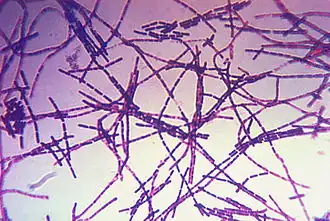

Erreger

Der Milzbranderreger, Bacillus anthracis, gehört zur Gattung Bacillus (sporenbildende, aerobe Stäbchenbakterien) innerhalb der Familie Bacillaceae. Er ist ein etwa fünf bis sechs µm (1 µm = 0,001 mm) langes, grampositives, unbewegliches, sporenbildendes Stäbchen, das in Körperflüssigkeiten kurze, in der Kultur längere kettenförmige Verbände bildet („Serpentinen“- oder „Medusakopf“-Form). Im Tierkörper ist die Bakterienzelle von einer deutlichen Kapsel (bestehend aus D-Glutamat) umhüllt, während in der Kultur in der Regel keine Kapselbildung erkennbar ist. Außerhalb des Tierkörpers, in Anwesenheit von Sauerstoff und bei Temperaturen von 12 bis 43 °C, bilden sich Sporen (Dauerformen), deren Größe etwa 0,5 bis 1,2 µm beträgt.